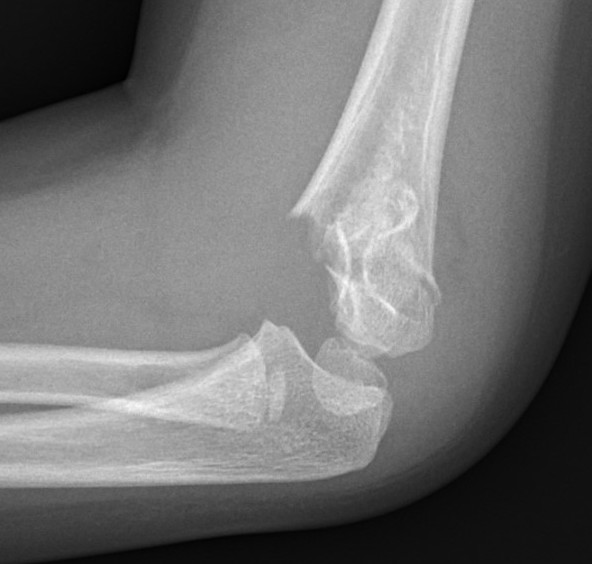

Lateral Xray

Position for good lateral

- thumb vertical

- hand above elbow

Anterior angulation

- shaft - condylar axis

- normally 40o

Lines

Anterior humeral line (AHL)

- should pass through middle of capitellum

Radio-capitellar line

- pass through capitellum

Teardrop

- shadow above the capitellum

- anterior dense line: posterior margin of the coronoid fossa

- posterior dense line: anterior margin of the olecranon fossa

- inferior portion: ossification center of the capitellum

6. Check lateral image

- lock elbow in flexion and rotation

- externally rotate the shoulder

- ensure that the anterior humeral line is correct

- reduction of teardrop on lateral

- may need to increase the flexion